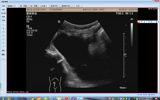

近日,我院超声科和妇科团队协作,成功完成一例超声引导下卵巢囊肿穿刺硬化治疗。 患者为一86岁老年女性,因“下腹部隐痛3天”至我院检查,彩超提示:盆腔内巨大囊性肿物,大小约112×74㎜。由于患者囊性包块较大且出现盆腔压迫症状,结合CA125、199等肿瘤指标及CT影像学检查,基本排除恶性可能。妇产科杨秀萍主任组织病...2023-03-23